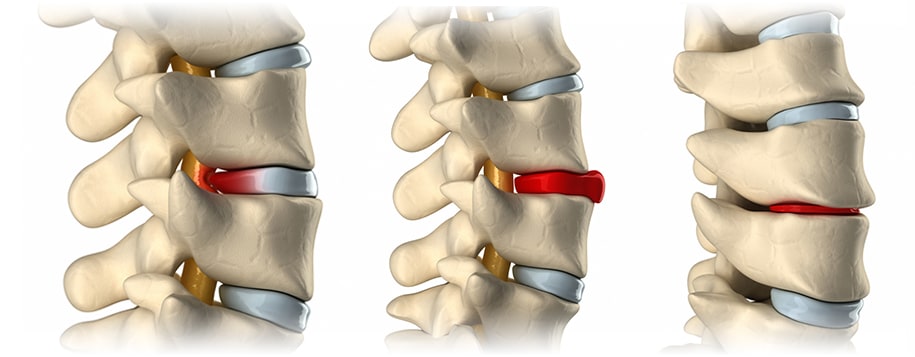

허리디스크는 척추 뼈 사이에서 충격을 흡수하는 디스크가 제자리에서 밀려나와 신경을 압박하면서 통증을 유발하는 질환을 의미합니다. 초기에는 단순 근육통처럼 뻐근하고 묵직한 느낌 정도로 시작되지만, 점차 엉덩이와 다리까지 저리고 당기는 방사통이 나타날 수 있습니다.